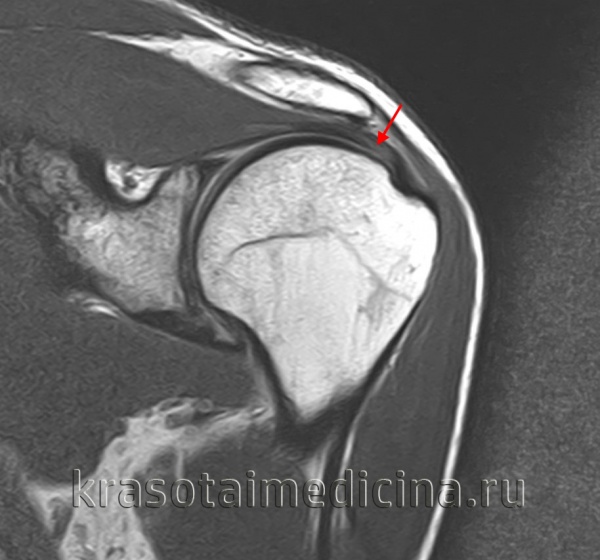

Диагноз повреждения ахиллова сухожилия выставляется на основании клинических данных, при необходимости может использоваться МРТ. В первые двое суток при незначительном расхождении концов сухожилия возможно консервативное лечение. На конечность накладывают гипс в положении максимального подошвенного сгибания сроком на 6 недель. При застарелых повреждениях и неудаче консервативной терапии показана операция.